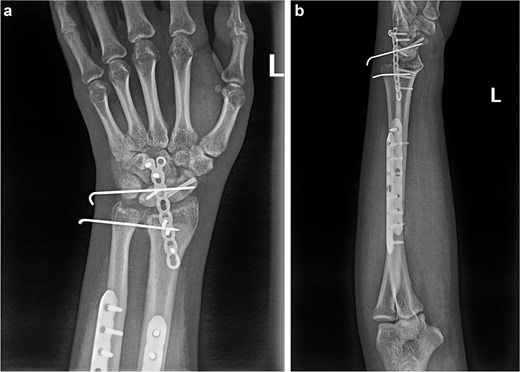

(a and b) Anterior and lateral views of the wrist joint after 6-month follow-up.